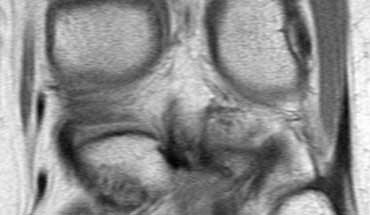

Đây là một trường hợp rách chân sụn chêm trong khác.

Lưu ý rằng sừng sau không còn bám vào xương chày.

Thay vào đó, có thể thấy một khoảng hở (mũi tên cong).

Những tổn thương rách này rất dễ bị bỏ sót khi người đọc nhầm tưởng sừng sau vẫn bình thường.